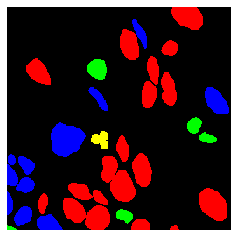

2.3 Image Annotations are an Effective Source of Privileged Information

We find that TriDeNT ♆ is effective not only for integrating additional sources of data, but also for manually determining the most useful aspects of the data which should be learned, where the user has some prior knowledge to incorporate into the dataset. This is intuitively the opposite of traditional machine learning approaches, where the user has to handcraft inputs to be passed to the model, and the model only learns from those features. With our approach, the user can manually handcraft inputs, such as the segmentation masks in this example, while still giving the model the flexibility to learn other features not known a priori to the user. The results in Table 2 demonstrate that TriDeNT ♆ is able to train encoders which retain the features of both the nuclei and the background/connective tissue. We see performance improvements of up to 42.4% compared to the privileged baseline, and up to 5.2% compared to the unprivileged baseline.

These results also suggest that, in the privileged Siamese case, the features that are learned are those relating to the shape of the nuclei, rather than any sub-nuclear features or features relating to the connective tissue which would enable better identification of tissue and cell types.

To further analyse the learned representations, we produce UMAP projections of the latent space labelled with the tissue types for the NCT tissue type classification task, as shown for CD3CD20 and SMA in Figure 4(a), and for all SegPath stains in Figures S8 and S9. These figures make the reasons for the varying performance of the privileged Siamese model more apparent. For stains with better performing privileged Siamese models, such as SMA, the UMAPs are very similar between Siamese methods and TriDeNT, with well-differentiated tissue type clusters. In those with worse performance, such as ERG, the tissue types are poorly differentiated, often with only adipose and background forming distinct clusters from the other classes. On closer inspection, it is notable in these projections that TriDeNT ♆ produces more well-defined and separated clusters in general than Siamese networks. This is further evidenced in Figure S7, where TriDeNT ♆ is shown to identify clusters with overexpression of a given gene significantly more effectively than an unprivileged Siamese model.

We also analyse the activation maps for each model using GradCAM as described in section S3. This offers more insight into the areas of the image which are contributing most heavily to the models’ representations. In Figure 4(b) we present some representative examples, however, a larger selection which was chosen at random is presented in Figures S10 to S25. The larger selection makes it easier to see the emergent patterns, including that privileged Siamese models tend to mainly identify features which are strongly present in both inputs, while unprivileged Siamese models tend to learn more diffuse features that are not specific to one cell phenotype or image region. TriDeNT ♆ incorporates both sets of features, learning both features specific to the privileged data and more the general features associated with unprivileged Siamese networks.

We can see in Figure 4(b) panel A that for ERG, the privileged Siamese model focuses almost exclusively on any nuclei which could be endothelial cells. As there are very few endothelial cells in the dataset, it could be an effective strategy to identify anything that could potentially be an endothelial cell to minimise the difference between the representations of the H&E model and the IF mask model. In the corresponding unprivileged Siamese image, we see that the model identifies some of these nuclei, albeit less strongly, but also focuses heavily on the other tissue and even the background, while strongly fixating on two spots of debris in the center of the image. This model has less ‘incentive’ to learn the weak features related to endothelial cells as these occur rarely and are not easy to detect, while more generic strong features such as the presence of connective tissue and the prevalence of background are more common and predictable from augmented images. We see that TriDeNT ♆ combines these two feature sets, strongly identifying nuclei while also identifying the connective tissue.

In panel C we see a similar pattern, with the privileged Siamese model fixating solely on the nuclei, while the TriDeNT ♆ model takes a more balanced approach. The unprivileged Siamese model appears to focus on a single cluster of nuclei while neglecting others, and similarly identifies an area of fibroblasts with its distinctive pattern but does not others.

In contrast to panels A and C which represent models with poor privileged Siamese results, panels B and D represent models whose privileged Siamese results were comparable to both TriDeNT ♆ and even the supervised baseline. It is therefore interesting to note that there are far more similarities between the privileged Siamese and TriDeNT ♆ models in both cases. Particularly in panel B, TriDeNT ♆ and the privileged Siamese model return virtually identical heatmaps, with both strongly identifying epithelial nuclei and neglecting the same areas of connective tissue. The unprivileged model in this case appears to focus solely on the centre of the image, giving a significantly different heatmap to the other panels.

Panel D again shows the previous pattern, with the privileged Siamese model identifying the features strongly present in the privileged data – fibroblasts – while neglecting the nuclei present. TriDeNT ♆ also strongly identifies the connective tissue, but, unlike the privileged Siamese model, does not completely neglect the nuclei. The unprivileged Siamese model primarily identifies background, and does not appear to identify the nuclei in this example.

S2.4 PanNuke Dataset

We next evaluated the models’ abilities to detect neoplastic cells using the PanNuke dataset [64]. A neoplasm is a type of abnormal and excessive growth of tissue, which can be either benign or malignant. PanNuke is a pan-cancer dataset of px H&E patches with paired nuclear segmentation masks, with six classes: Neoplastic, Non-Neoplastic Epithelial, Inflammatory, Connective, Dead and Background. We evaluated the model on classifying patches containing neoplastic and non-neoplastic cells. Following [65], we denoted patches containing no neoplastic cells as non-neoplastic, and patches containing at least 10 neoplastic cells where at least 30% of all cells in the patch are neoplastic as neoplastic patches. This yielded a dataset with three folds of sizes 2205, 2090, and 2283 respectively. We used the first two folds for training and the third fold for testing, and provide three-fold cross-validation in Table S12 to justify this.

Segmentation models typically learn fine-grained details such as the exact locations of features, which comes at the cost of identifying features in the images. In contrast, the augmentations used in self-supervised models discourage them from learning to identify the exact locations of features and similarly precise image properties, as these can change under augmentation. This enables self-supervised models to transfer more robustly to different tasks, as was shown in [19], where a U-Net segmentation model was demonstrated to perform significantly worse when transferred to a classification task than a comparable self-supervised model. Given that the objective of feature extraction models is to learn these more abstract features, rather than the precise properties found by segmentation models, we evaluated only on the neoplastic classification task, rather than the segmentation task.